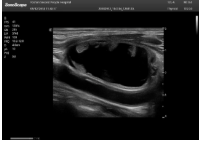

2相控陣探頭

探頭面是平面,接觸面小,近場視野最小,遠(yuǎn)場視野大,成像視野呈扇形,適用于心臟。

心臟探頭通常按應(yīng)用人群劃分為成人、兒童、新生兒三類:(1)成人心臟位置最深、搏動速度慢;(2)新生兒心臟位置較淺、搏動速度最快;(3)兒童心臟的情況介于新生兒與成人之間。